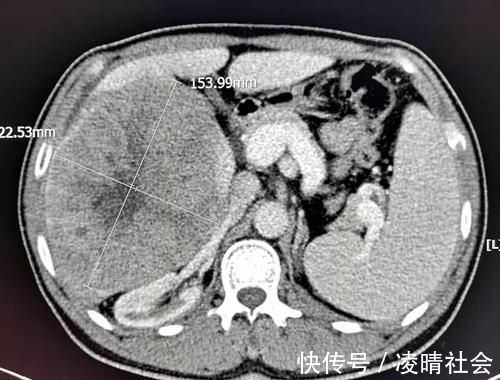

像这位男性病人,49岁查体发现大肝癌,长约15厘米,长满半个肝脏了。病人很配合治疗,也不怨天忧人,手术后已经5年了,没有复发: